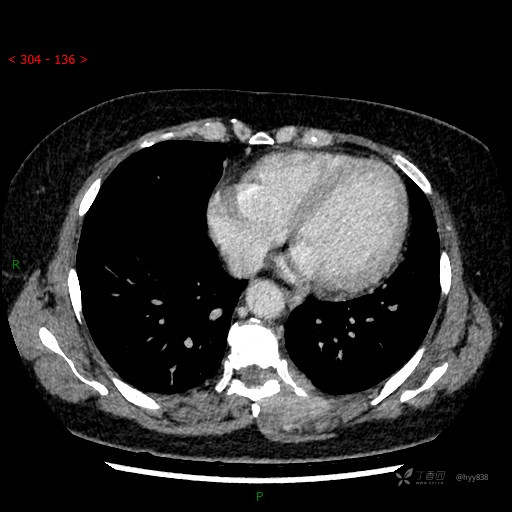

增强